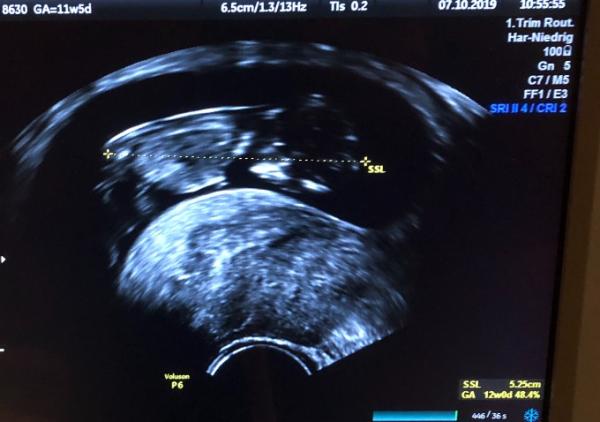

Heute war die erste große Untersuchung. Es war alles super. Ich konnte die zwei Gehirnhälften sehen und die Wirbelsäule . Das kleine hat geschlafen, sie hat es dann geweckt um es noch von der Seite zu sehen, davor nur von vorne. War unglaublich süß, bin total verliebt. Es ist 5,2cm groß

Bild zu Heute FA-Termin gehabt - Forum für April - Mamis